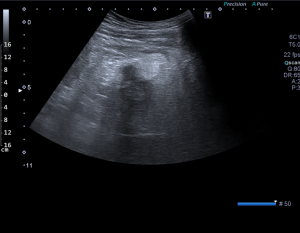

Vyšetření provádí erudovaný lékař, který pro danou vyšetřovanou oblast zvolí vhodnou ultrazvukovou sondu a nastaví optimální parametry přístroje. Pacient při vyšetření leží na vyšetřovacím stole a dodržuje pokyny lékaře. Nejčastěji se vyšetření provádí vleže na zádech, na břiše nebo na boku. Kůže pacienta se ve vyšetřované oblasti pokrývá vrstvou gelu pro sonografii. Lékař plynule pohybuje po pacientově těle ve vyšetřované oblasti ultrazvukovou sondou a při tom sleduje obraz na monitoru. Vyšetření se provádí v různých rovinách daných postavením sondy, někdy i v různých polohách pacienta. Během vyšetření lékař v případě potřeby provádí různá měření. Při vyšetření asistuje vyškolená sestra, která pomáhá především s odstrojením a uložením pacienta, provádí administrativní úkony a řídí objednávání pacientů. Před vyšetřením sestra nebo lékař vysvětlí pacientovi stručně, jak vyšetření probíhá a co je jeho cílem, eventuelně rozptýlí případné obavy pacienta z vyšetření. Na závěr vyšetření pak lékař pacientovi co nejsrozumitelněji vysvětlí zjištěný nález, jeho závažnost a případné další důsledky. Obrazová dokumentace je zhotovena tiskem na speciální papír, eventuelně je provedena digitální archivace obrazu.

Ultrazvukový přístroj

Naše pracoviště je vybaveno přístrojem Aplio 300 od firmy Toshiba, který je vybaven konvexními a lineárními sondami.